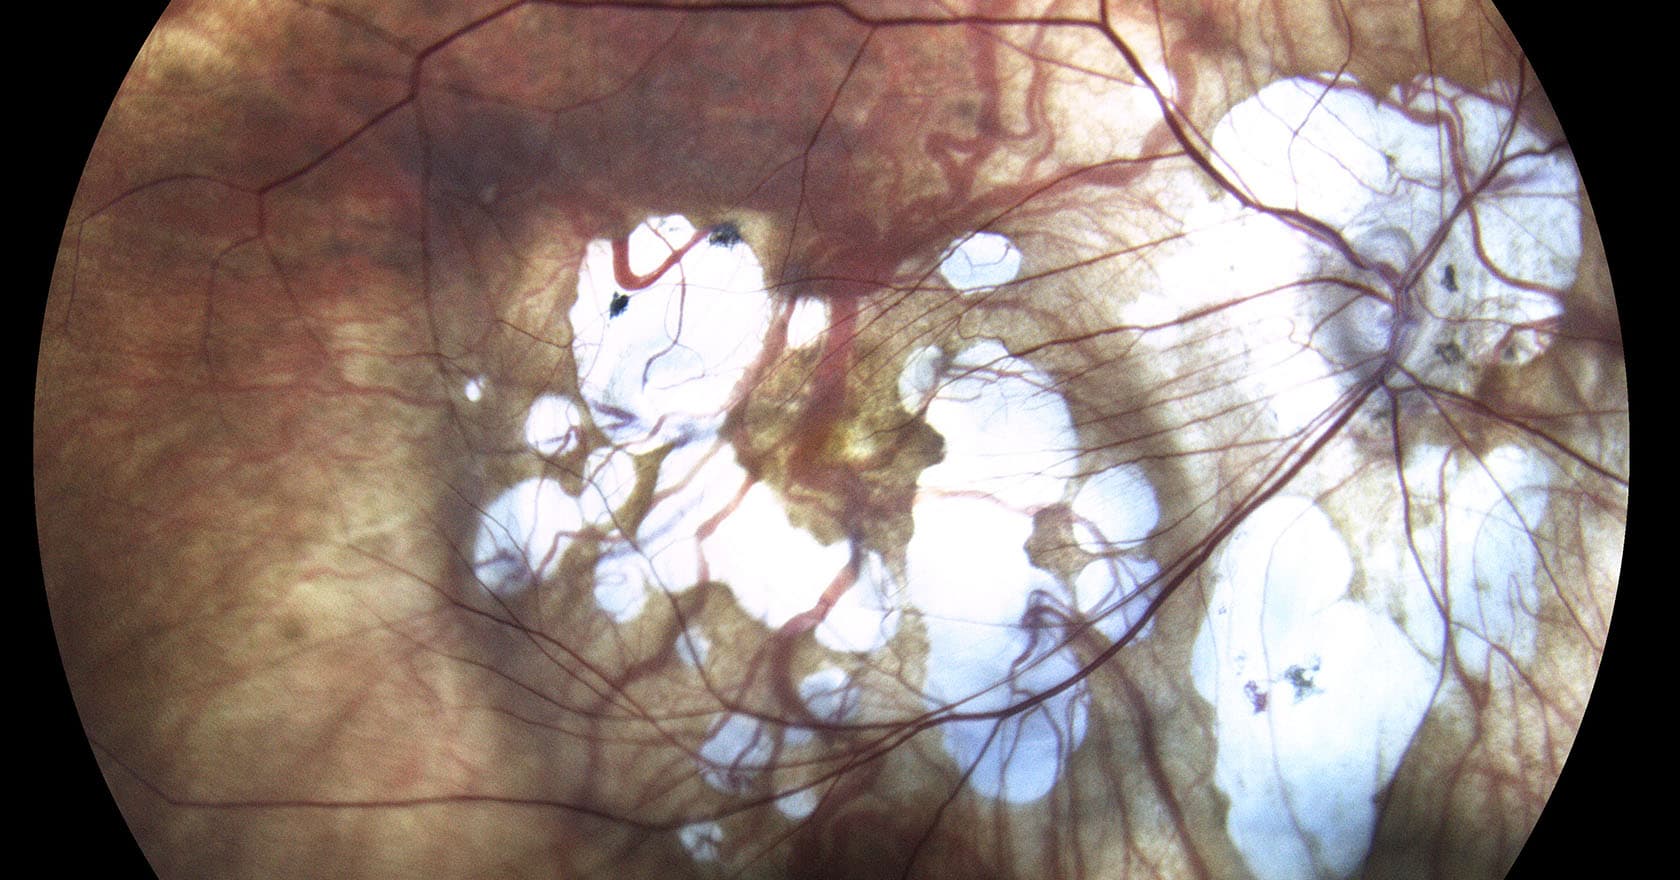

La myopie forte est une maladie touchant également la rétine entraînant plusieurs complications telles que la formation de vaisseaux anormaux sous la rétine, la cataracte, le décollement rétinien, le glaucome et les pathologies maculaires.

- Un examen de fond d’ une rétinophotographie pour voir si la rétine s’est décollée ou non.

Ces examens permettent à l’ophtalmologiste de convenir d’un traitement adéquat afin d’aider le patient. Il est important de bien observer la rétine lors du diagnostic car c’est la partie de l’œil la plus touchée par la myopie forte. Les complications rétiniennes possibles sont à traiter rapidement.